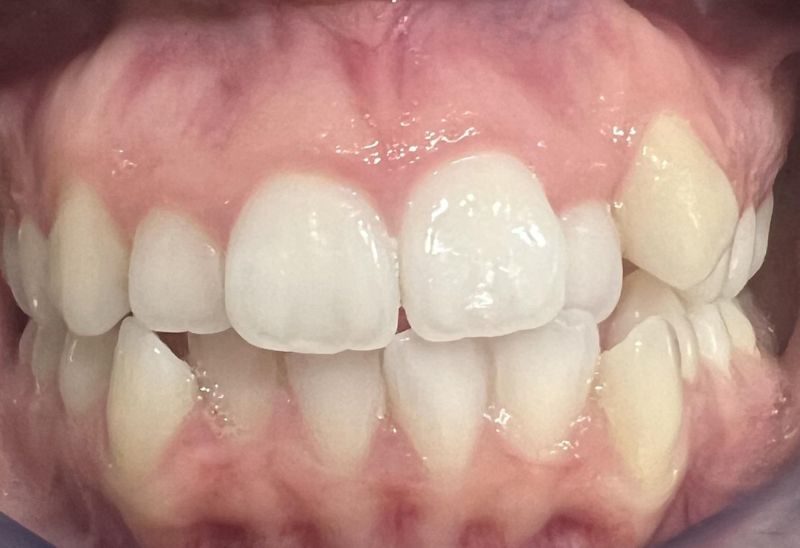

Prima e dopo l'apparecchio invisibile

In questa sezione mostreremo risultati reali ottenuti con l’ortodonzia invisibile a Roma. I cambiamenti riguardano non solo i denti, ma anche l’armonia del viso, la postura orale e l’autostima.